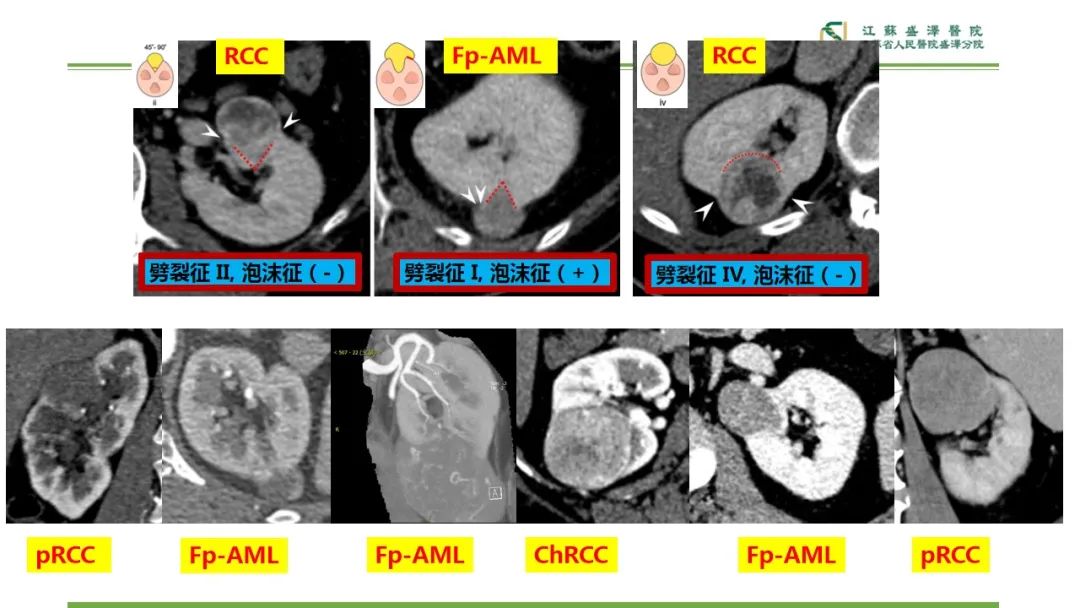

【PPT】肾脏实性肿瘤的良恶性鉴别--影像诊断思路分析-7